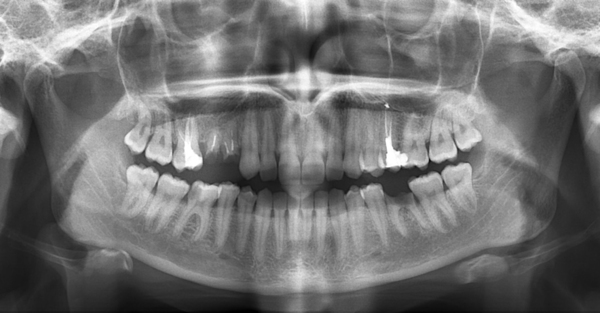

По выраженности и глубине рентгенологических проявлений пародонтит делится на начальную, среднюю и тяжёлую стадию:

- На начальной стадии пародонтита высота альвеолярного отростка снижена только на 1/3 от длины корня. На снимке наблюдается разволокнение межальвеолярных перегородок с дальнейшим полным исчезновением. Периодонтальная щель в пришеечной области симметрично расширена с одной стороны. По мере прогрессирования, обострения воспаления резорбция межальвеолярных перегородок усиливается.

Фото 1. Пародонтит начальной стадии на рентгенограмме. Десны поражены не сильно, корни зубов практически не оголены.

- При пародонтите средней тяжести высота межальвеолярных перегородок снижена уже на 1/2 от длины корня. Трабекулярный рисунок кости смазан, прозрачность повышена. Резорбция костной ткани проходит вдоль корня, образуются пародонтальные карманы. У одного и того же пациента наблюдаются разные типы резорбции.

- Для тяжёлой степени заболевания характерно неравномерное убывание кости межальвеолярных перегородок более чем на 1/2 длины корня. А корни зубов оголены больше чем на половину от своей длины.